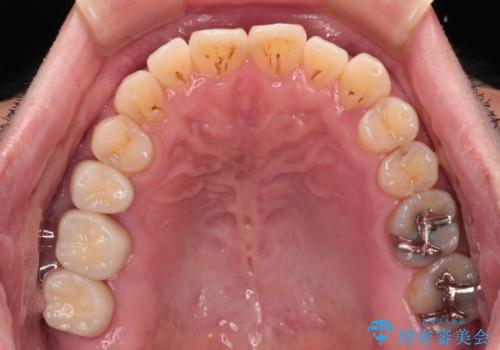

まずは仮歯に置き換え、歯周ポケットを除去するための外科処置(歯肉弁根尖側移動術)を行い、治癒を待ってセラミッククラウンにて補綴治療を行うこととしました。

外科処置後は知覚過敏症状が酷くなることが多いのですが、術後は比較的落ち着いており、スムーズに処置を進めることができました。